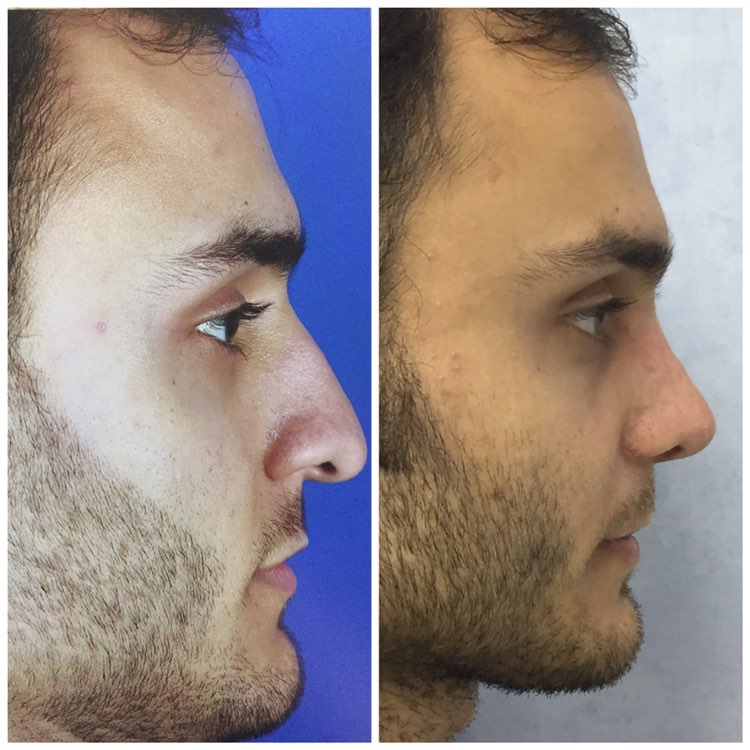

دکتر عیسی عبدی در رشت

دکتر عیسی عبدی در رشت

– متخصص جراحی فک , پلاستیک صورت و بینی

دکتر عیسی عبدی در رشت

جراحی فک , پلاستیک , صورت وبینی